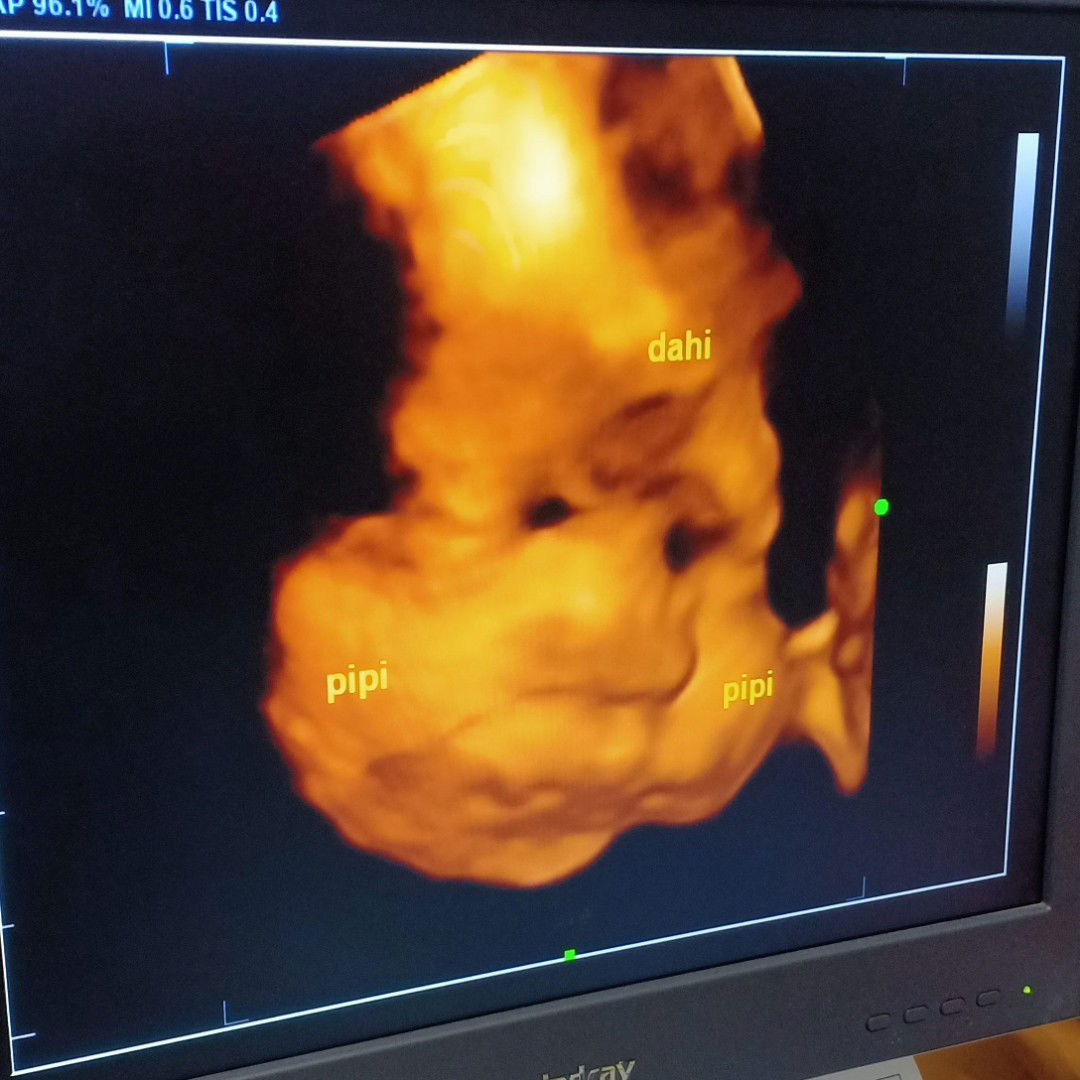

34weeks yg nano nano nikmatnya

Sharing yuk bun yg udah trismester 3 udah ngerasain apa aja... Saya udah 34weeks ... nyeri2 sedap di bagian miss v , tulang punggung berasa mau patah,, Tidur udah engap bgt ,, susah tidur gak enak semua🤭🤭 Tapi menikmati sekali semester akhir yg nano-nano ini... Bunda udah ngerasain apa aja???? #bantusharing #justsharing #34weeks